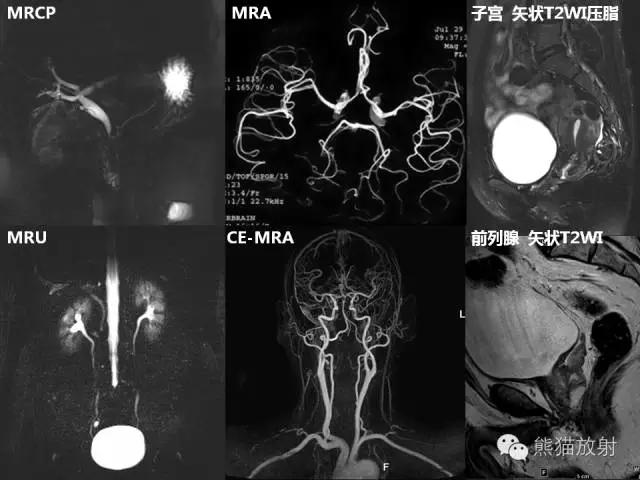

浅析核磁共振里的T1,T2参数

1、T1观察解剖结构较好。

2、T2显示组织病变较好。

T1加权成像、T2加权成像

T1加权成像(T1WI)----突出组织T1弛豫(纵向弛豫)差别

T2加权成像(T2WI)----突出组织T2弛豫(横向弛豫)差别。